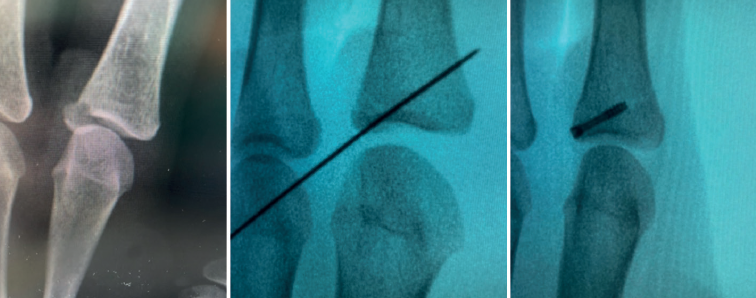

- Fractures with avulsion of the insertion of the collateral ligament (Figures 2 and 3).

Once the fragments have been reduced, 0.8 or 1.0 Kirschner wires are used to maintain reduction (Figure 7). Sometimes we can only maintain reduction by applying a stop, to prevent the osteochondral fragment from collapsing. Depending on the fracture pattern and the surgeon's preference, we can use conventional screws, cannulated screws, etc. (Figures 8 and 9).